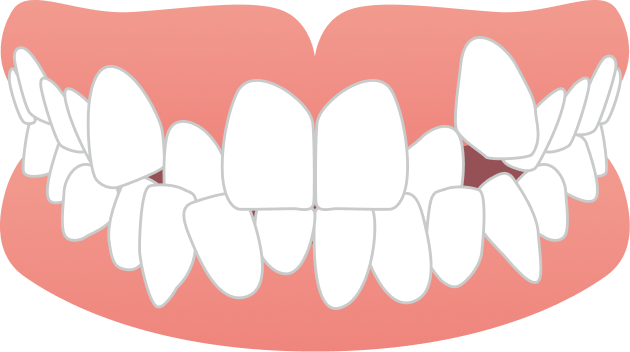

20代女性 出っ歯と噛み合わせが気になる

「前歯が出ているのが気になる」「前歯で噛めない」というお悩みでご来院されました。

BEFORE

| 主訴 | 出っ歯、前歯で噛めない(噛み合わせが悪い) |

ガタガタ・八重歯

ガタガタ・八重歯 出っ歯